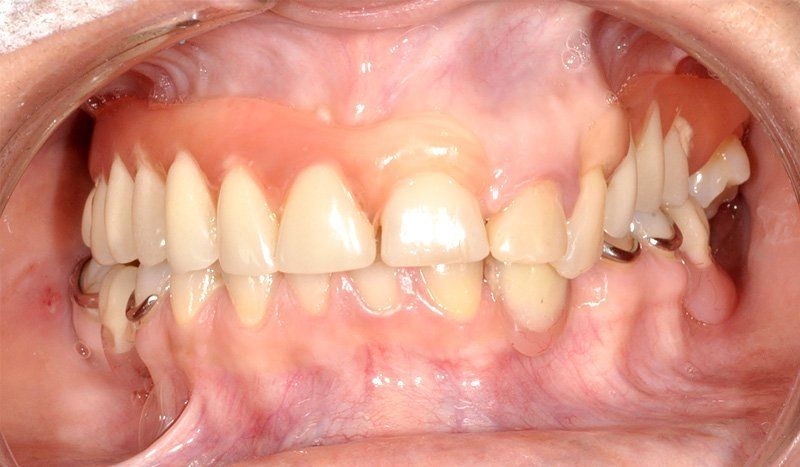

Sus beneficios son que se instalan con mayor tranquilidad para usarlos, no hay que sacárselo todas las noches, la gente queda con una mayor seguridad interna, mejora la autoestima, el humor y las relaciones interpersonales.

Porque se hace en pabellones certificados por la Universidad de Chile. Son dependencias hechas única y exclusivamente para hacer intervención en sitios estériles. También se hace más cómodo y se pasa rápido el periodo de espera. Del momento en que se insertan los implantes debe transcurrir un período de tiempo de entre 4 a 6 meses si es en mandíbula o maxilar superiores respectivamente para que el tejido óseo cicatrice y logre integrarse a la superficie del implante